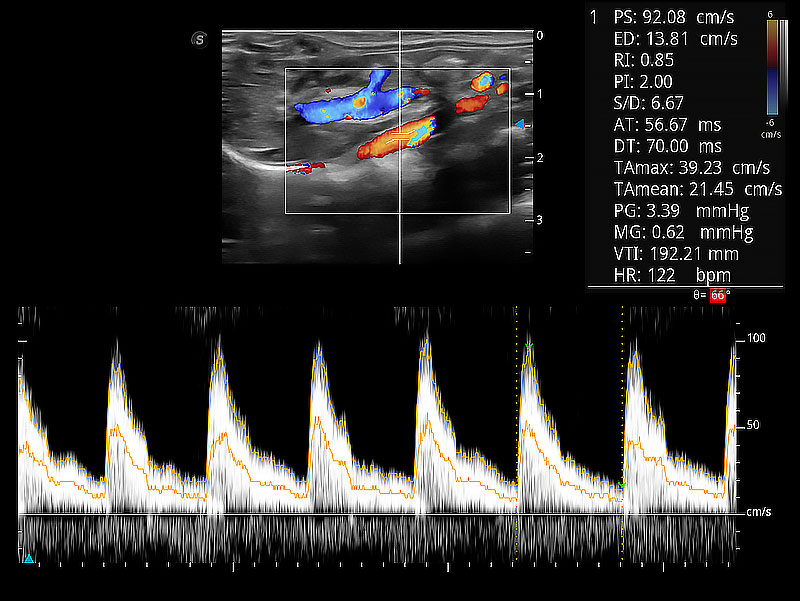

隨著取樣門位置改變,頻譜多普勒包絡(luò)可進(jìn)行自動眼蹤測量,且可自由配置測量的參數(shù)。